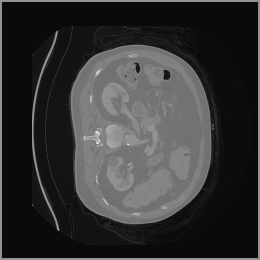

As shown in Figure 5, the generated slices exhibit high consistency across adjacent slices. The anatomical structures and semantic patterns are smoothly and coherently preserved between slices, indicating that our model is capable of generating 3D-consistent synthetic images rather than isolated 2D slices.